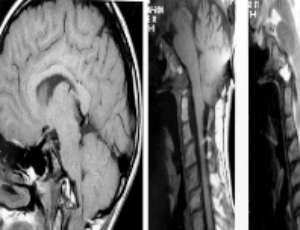

Craniovertebral junction abnormalities in children: Surgical, anesthetic and intensive care implications

The craniovertebral junction is unique and the most complex of the axial skeleton in multiple aspects; embryology, anatomy, pathology and kinematics. A surgical physiological approach to management of its abnormalities was instituted at the University of Iowa Hospitals & Clinics (UIHC) in 1977 and has been the accepted treatment algorithm worldwide.

J Clin Anesth Intensive Care, 2021, Volume Volume 2, Issue Issue 2, p31-41 | DOI: 10.46439/anesthesia.2.011